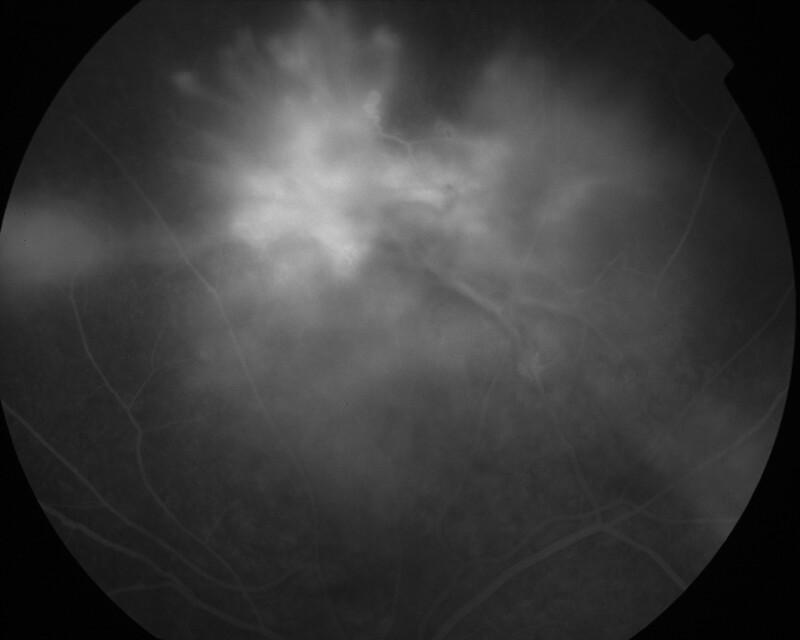

IM000037.jpg